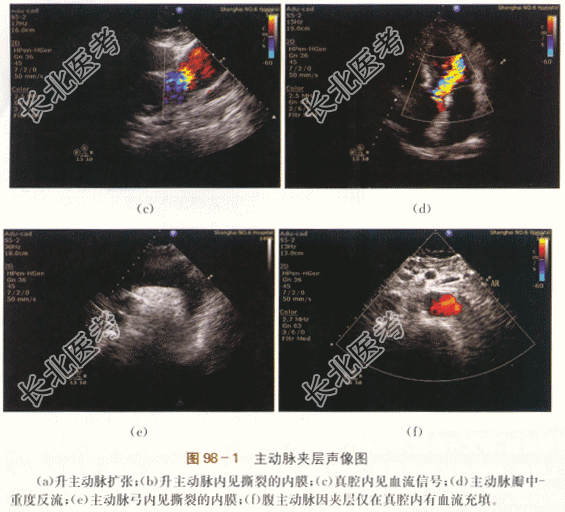

- [材料题] 患者,男性,62岁,因“胸前区疼痛6小时”就诊。患者下午5时左右,无明显诱因出现胸前区针刺样疼痛,向背部放射,伴大汗淋漓,伴头晕,无胸闷,无头痛,无恶心呕吐,无气急,无心悸等不适,未就诊,休息后症状无缓解,胸痛症状较前明显,向中下腹部腰部放射,伴胸闷、头晕,无恶心呕吐,无气急等,下午7时到我院急诊。体格检查:患者血压110mmHg/67mmHg,神志清醒,气平,无贫血貌,双肺听诊呼吸音清,肺底未及啰音。心浊音界大致正常,心率52次/min,律齐,P2=A2,主动脉瓣听诊区可及3/6级舒张期吹风样杂音。腹壁柔软,无腹部压痛。双下肢无水肿。实验室检查及特殊检查:血WBC升高,RBC及Hb下降,N增高,ESR增快,D-二聚体升高。心肌酶谱升高,蛋白尿。心电图:窦性心律,Ⅰ度房室传导阻滞,LⅢ呈QR型。影像资料: